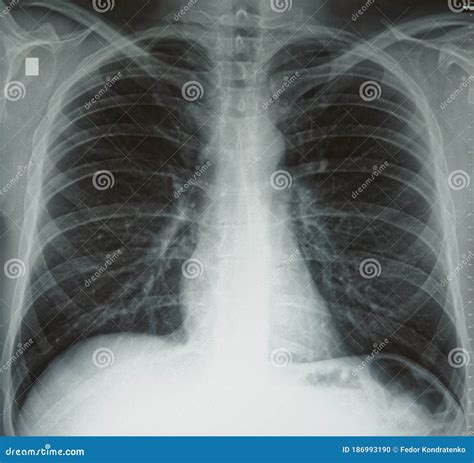

Le diagnostic du syndrome obstructif repose sur plusieurs éléments : l'anamnèse médicale, l'examen physique et les tests de la fonction pulmonaire. Un patient fumeur souffrant d'un syndrome obstructif doit impérativement arrêter de fumer. Le diagnostic de BPCO est établi par spirométrie, bien que d'autres tests de la fonction pulmonaire puissent être utiles. Une radiographie thoracique est souvent réalisée pour rechercher une hyperinflation et exclure d'autres pathologies pulmonaires, bien que les lésions de la BPCO ne soient pas toujours visibles. La distinction entre bronchite chronique et emphysème n'est pas toujours cruciale, car ces deux pathologies coexistent fréquemment. La gravité de l'obstruction du débit aérien est le facteur déterminant pour évaluer l'état de santé et le fonctionnement du patient.

Dans la BPCO peu sévère, l'examen clinique peut ne révéler rien d'anormal. À mesure que la maladie progresse, des sifflements peuvent être audibles à l'auscultation, ou une diminution des bruits respiratoires normaux. Une expiration prolongée peut être constatée. La mobilité du thorax diminue, et le patient peut solliciter les muscles du cou et des épaules pour respirer. Dans les stades précoces, la radiographie thoracique est généralement normale. Les stades plus avancés peuvent montrer une distension pulmonaire excessive, un amincissement des vaisseaux sanguins ou la présence de bulles, suggérant un emphysème. Les médecins peuvent identifier une obstruction au flux ventilatoire par spirométrie, mesurant la quantité d'air expiré et sa vitesse. Une baisse du volume expiratoire maximal en une seconde (VEMS) est caractéristique.